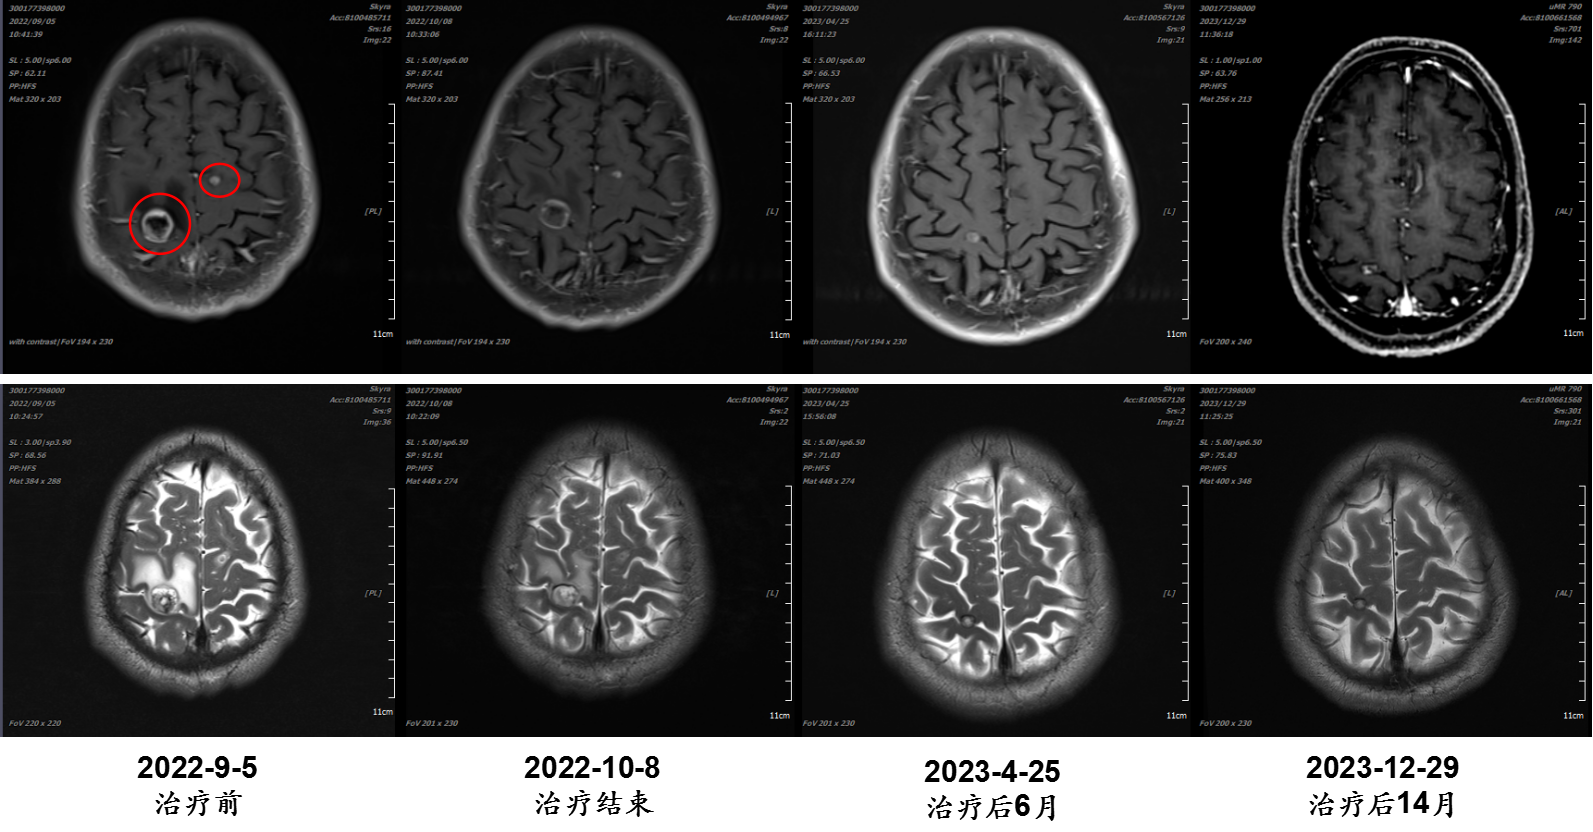

04 病例四

张某某,男,57岁;诊断:食管癌多发脑转移;治疗时间:2022/9/20至2022/10/7。

病例提供医生:王馨 科室:放疗中心一科(国际一部)